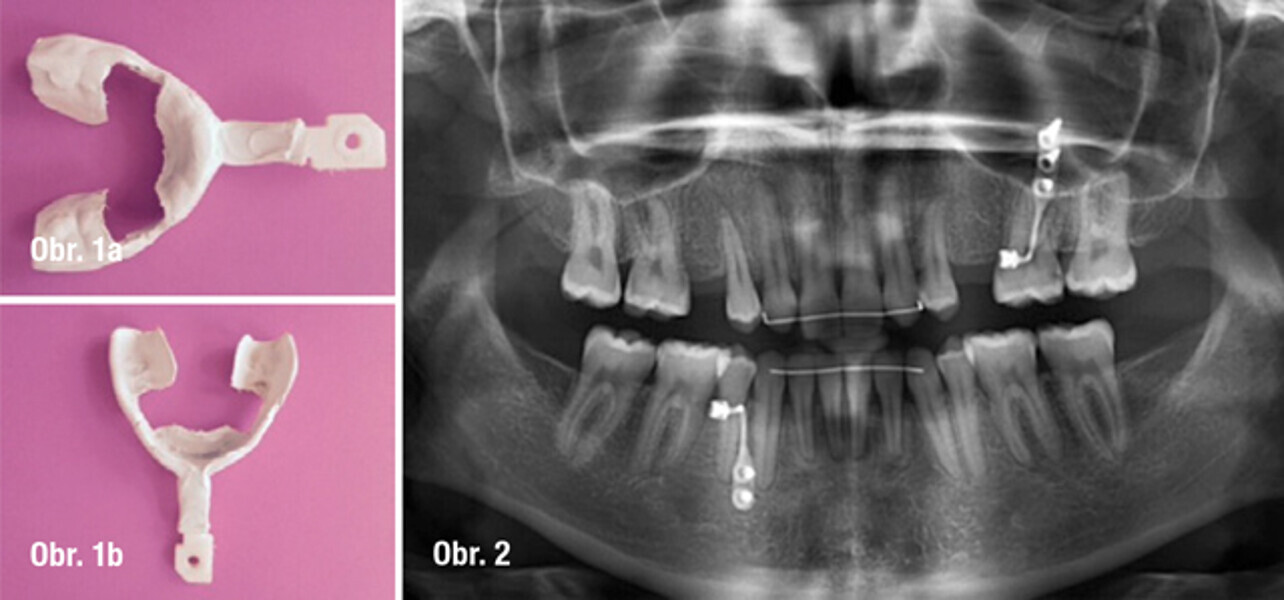

Implantace pomocí dynamické navigace s okamžitým zatížením